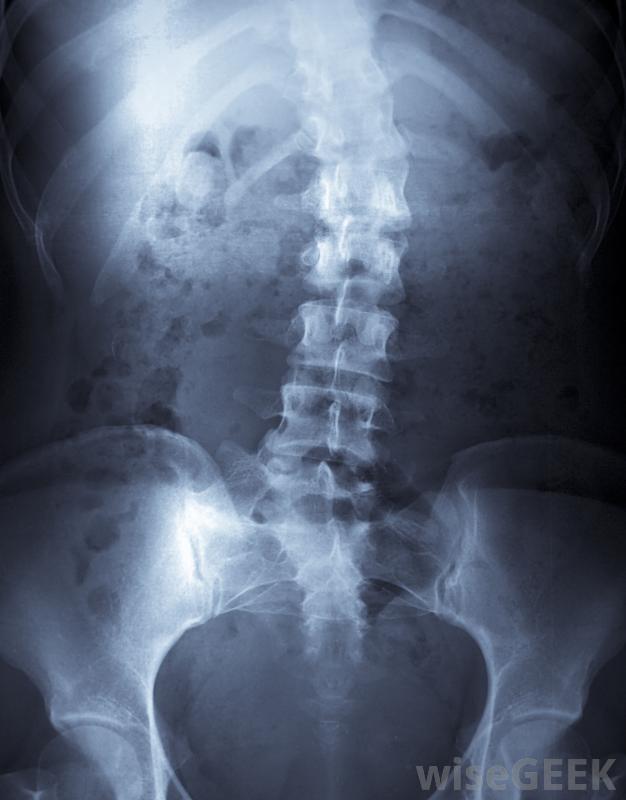

患有Klippel-Feil综合征的人可能会经常头痛颈部有7个椎骨,在Klippel-Feil综合征中,至少有两个椎骨不能形成正常情况下允许椎骨移动的分离。两个以上的椎骨也有可能融合在一起;融合的越多,症状越严重。问题的外在症状可能包括背部发际线较低,颈部比正常情况下更远,以及相对较短的颈部和不对称的面部特征。在Klippel-Feil综合征患者中,脊柱侧凸的发生率很高。由于脊柱融合发生在出生前,这种情况一直存在

Klippel-Feil综合征患者脊柱侧凸的发生率很高颈部和脊柱的健康对身体其他部位的健康至关重要;由于这种关系,Klippel-Feil综合征也有一些相关的疾病。一个人可能会有吞咽或咀嚼困难,经常头痛或头晕,并表现出不同程度的视力模糊或耳聋。有许多症状和缺陷与此相关;有些人可能有腭裂、颅内肿瘤或泌尿系统异常,严重到肾脏缺失